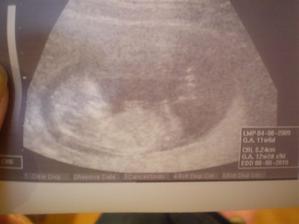

21.9. 2009 - kontrola dopadla dobre, uz nekrvacam, hematom sa nezvacsuje, dala som krv na vstupne testy 8.10 - dalsia poradna - som 9+2 tt - prcek ma uz 2,57 cm - valibuk 🙂)) , sice sa moc nehybal, ale srdiecko bilo ako zvon. Vsetko je ok, akurat ma uz asi mesiac trapia mocove cesty, takze vzorka mocu poputuje na kultivaciu............................